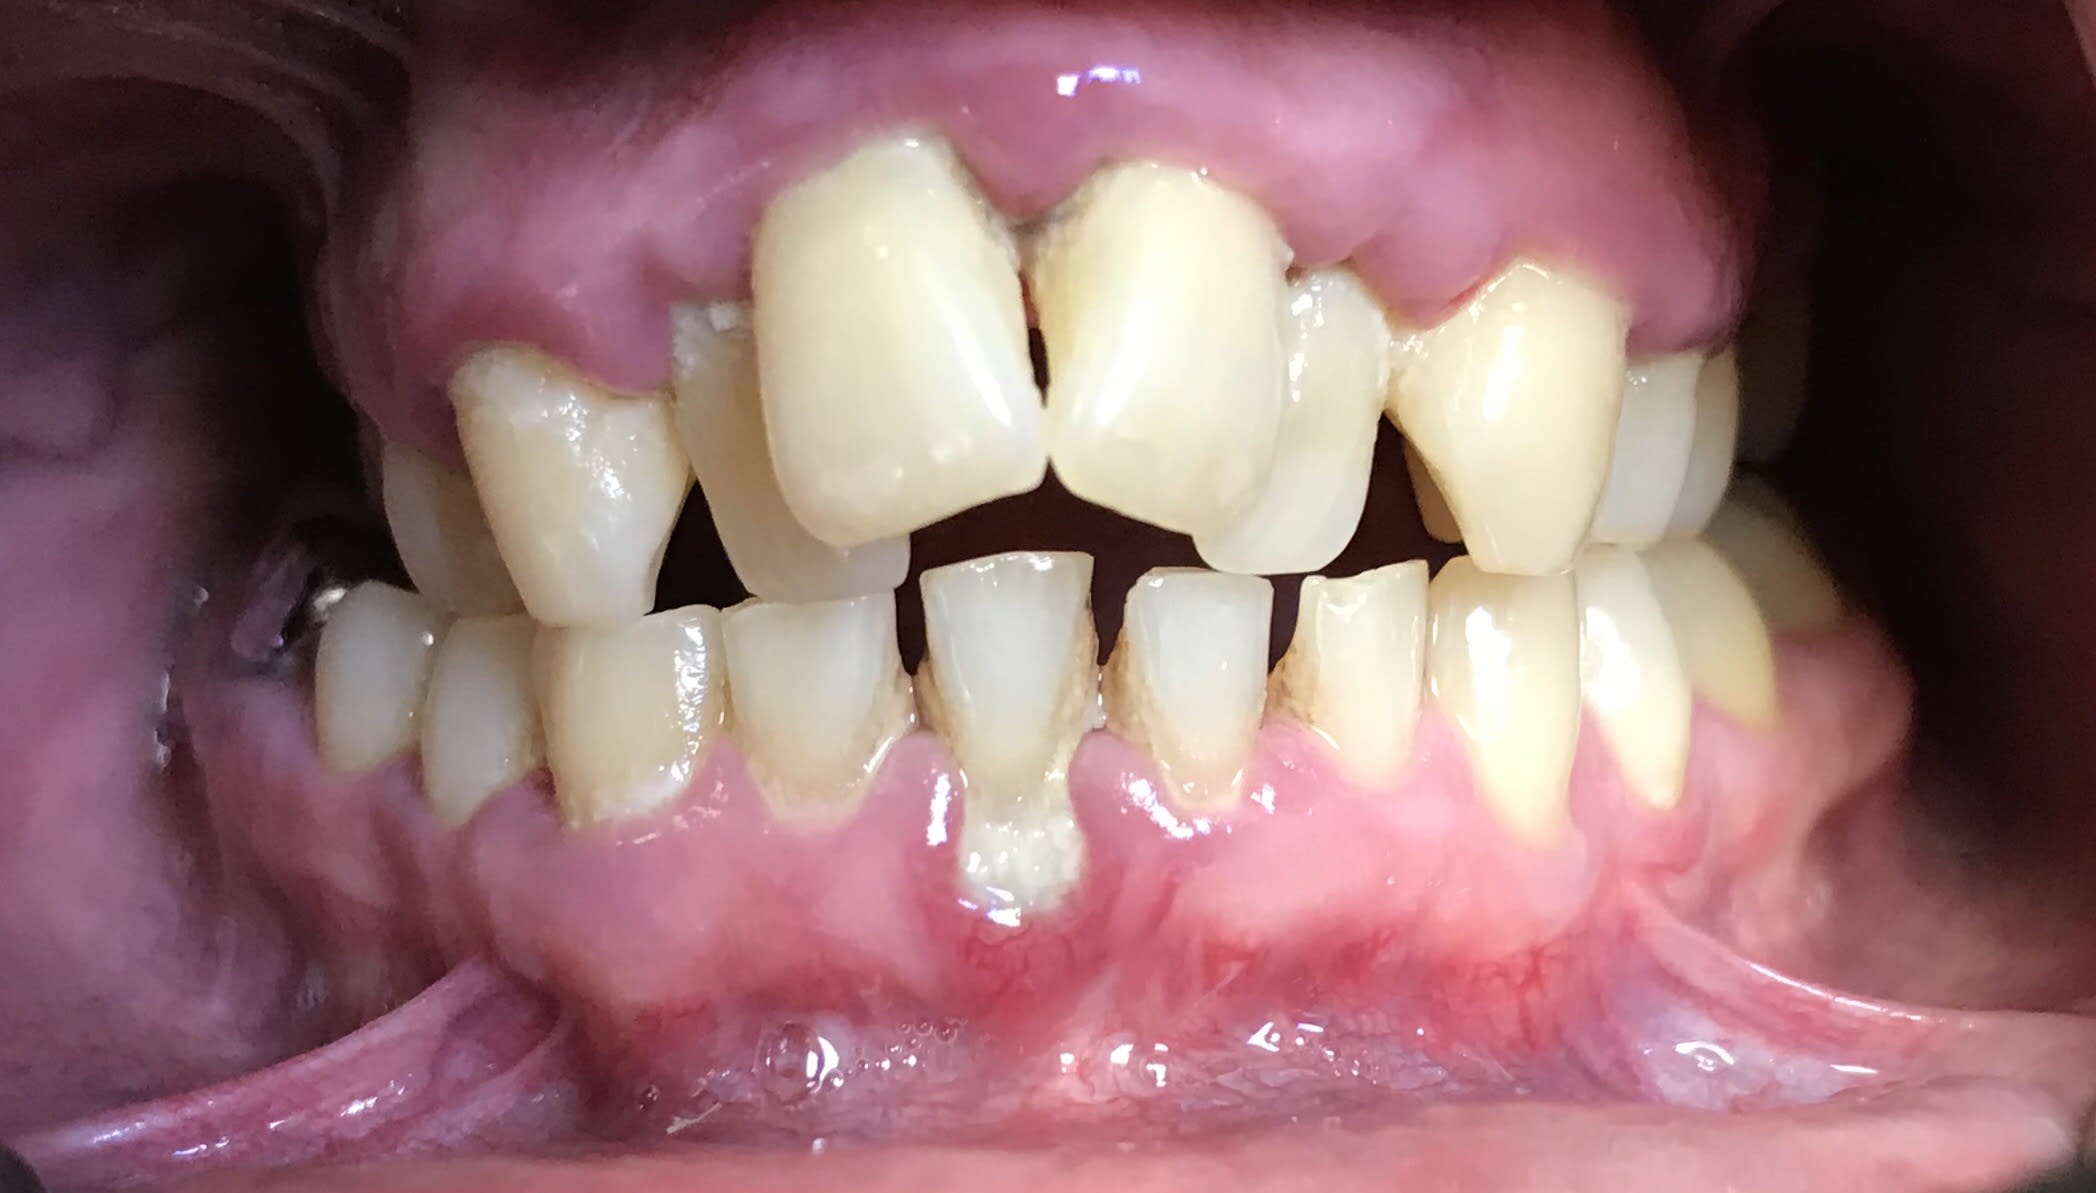

Ça c’est un cas qui s’apparente au cas du nouveau . Le problème dans ce genre de cas traité uniquement prophétiquement c’est qu’on n’obtient pas forcément une meilleure occlusion :) .

Dans le cas du nouveau il faut vraiment faire une intervention osseuse ++++, encore plus que sur celle-ci

Sur celle là il y a eu quoi ? Elongation ou bien impaction du bloc ant ?

Celle-ci c’était élongation et plusieurs implants en postérieur.

À la base elle était juste venue pour ne plus avoir de sourire gingivale. J’ai commencé par le secteur antérieur. Sauf que quelque part ses dents antérieures lui stabilisaient son occlusion. Aussitôt que je lui ai fait le secteur antérieur, qu’elle s’est plainte de ses articulations . Donc j’ai tout de suite posé des implants en postérieur et mis des couronnes , et aussitôt plus de problème. Il aurait fallu commencer par ça. Mais bon comme ils ne jurent que par l’esthétique, c’est toujours le problème. Et c’est une fois qu’ils sont en confiance que certains se décident à faire le postérieur.

"Aussitôt que je lui ai fait le secteur antérieur, qu’elle s’est plaint de ses articulations . "

Classique :-) et c est a cause des cingulums que tu lui as recréé . Avant elle n en avait pas ( plus) .